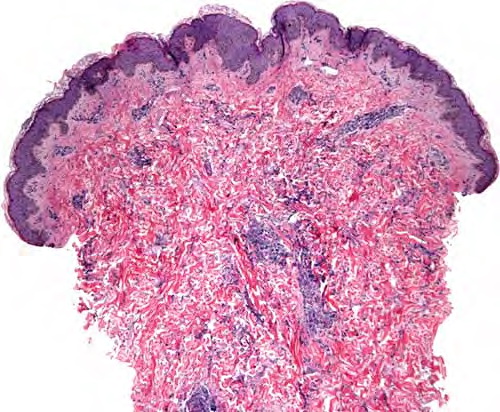

Interstitial granulomatous dermatitis = التهاب الجلد الحبيبومي الخلالي